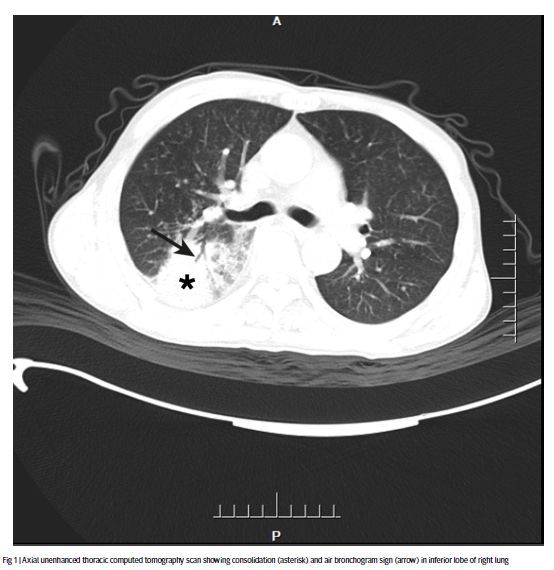

肺部计算机断层扫描(CT)结果如下图所示,显示右下肺肺叶实变。颅脑磁共振、脑脊液分析等其他检测结果均正常。

▲胸部ct轴位平扫显示右肺下叶实变(星号)和支气管充气征(箭头)(图片来源:参考资料[1])